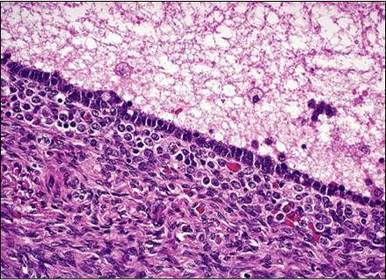

Diagnóstico e micro. Adenomiose. Glândulas endometriais na intimidade do miométrio (profundidade >2,5mm)